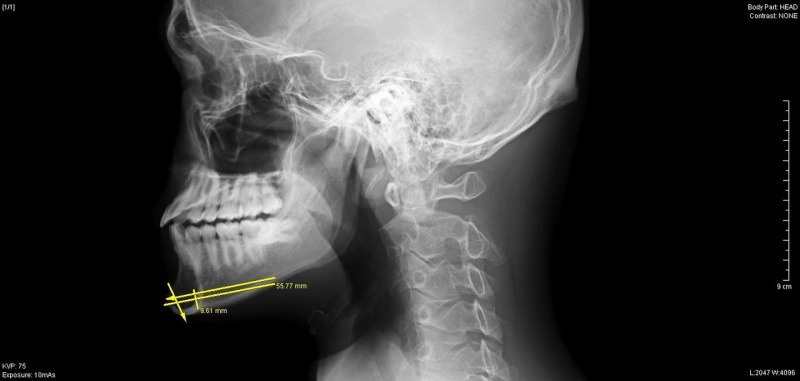

頭部レントゲン写真の側面写真で下顎骨の中央部より切り始め、

最大9mm切除にてデザインしました。